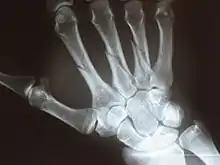

Metacarpal bones

Metacarpals shown in red. Left hand, anterior (palmar) view.